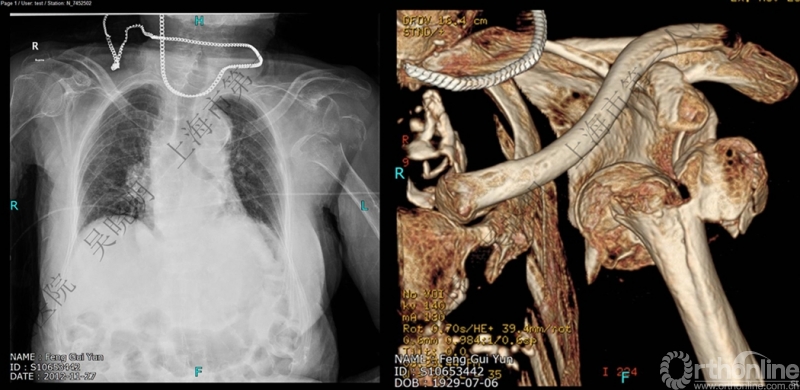

一:高质量的平片能否发现隐型解剖颈骨折?

常规X线难发现外科颈骨折

下图考虑为孤立性的大结节骨折?

看完片子,你会发现高质量的平片甚至3D CT也难以发现

X线看不清骨折线,三维CT也看不清